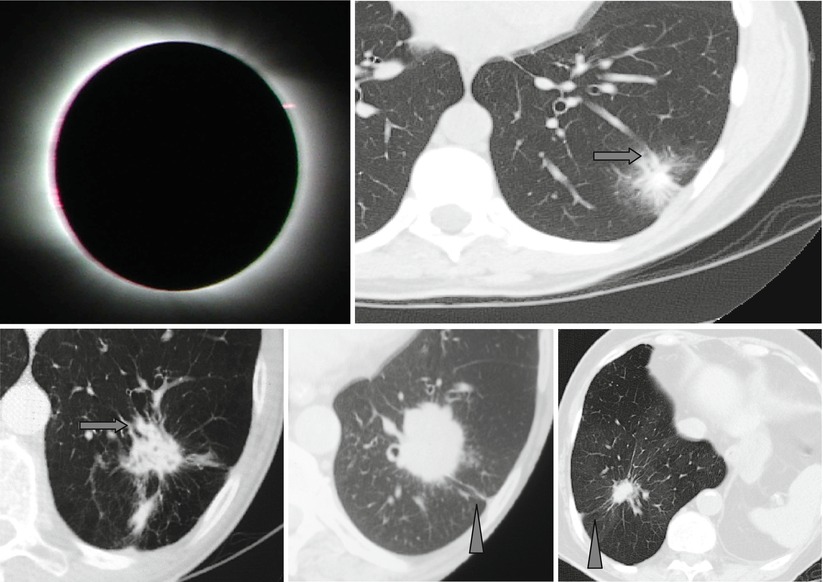

Corona Radiata Or Corona Maligna And Pleural Tail Sign Springerlink

The Radiology Assistant Covid 19 Imaging Findings